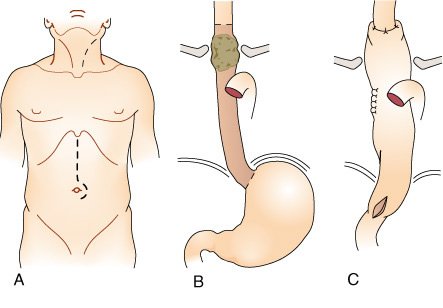

Existe quatro tipos de esofagectomia:

- transtorácica

- em bloco,

- transiatal

- videoassistida

Nenhuma delas não tem vantagem no que concerne à sobrevida relativa.

- A esofagectomia transtorácica compreende:

- uma laparotomia mediana para mobilização do estômago

- uma toracotomia direita para as lesões proximais, ou esquerda para lesões distais.

- A esofagectomia em bloco envolve ressecção completa do esôfago com uma dissecção ganglionar de dois (tórax e abdome) ou três (tórax, abdome e pescoço) campos através de laparotomia mediana, toracotomia direita e incisão cervical para a anastomose proximal do tubo gástrico no esôfago cervical remanescente.

- A esofagectomia transiatal requer incisão cervical para mobilizar o esôfago e realizar a anastomose proximal e, então, uma laparotomia mediana para mobilizar o esôfago e o estômago.

- A esofagectomia videoassistida utiliza a videolaparoscopia para mobilizar o estômago, VATS para mobilizar o esôfago e uma incisão cervical para a anastomose do tubo gástrico no esôfago cervical remanescente.

Esofagectomia Transiatal

A esofagectomia transiatal sem toracotomia foi desenvolvida em decorrência das complicações pulmonares e de deiscência intratorácica associadas à toracotomia necessária nas esofagectomias transtorácicas e em bloco.

Na esofagectomia transiatal, todo o esôfago torácico é ressecado através do hiato alargado e reconstruído com o estômago anastomosado ao esôfago cervical remanescente acima do nível das clavículas

Ao realizar a esofagectomia transiatal, o cirurgião remove os linfonodos cervicais, intratorácicos e intra-abdominais acessíveis para estadiamento, porém não pode ser realizada uma ressecção em bloco dos linfonodos e tecidos adjacentes.

Esofagectomia Transtorácica

Enquanto a esofagectomia transiatal focaliza a redução da morbidade pós-operatória por evitar a toracotomia, a esofagectomia transtorácica permite completa dissecção ganglionar sob visualização direta da massa tumoral e dos tecidos adjacentes, com completo estadiamento do tumor e a possibilidade de maior morbidade peroperatória.

O esôfago repousa no lado direito do mediastino, exceto em seu terço distai, que se curva à esquerda. Além disso, o arco aórtico repousa sobre a lado esquerdo do esôfago proximal e obscurece a visualização durante a ressecção de um tumor do terço médio a superior.

A abordagem cirúrgica tradicional para carcinoma esofágico do terço distai tem sido a incisão tóraco-abdominal. O esôfago distai, o estômago proximal e os tecidos adjacentes, incluindo linfonodos, são ressecados e a anastomose gastroesofágica é realizada.

Esofagectomia em Bloco

Uma vez que muitos pacientes apresentam metástases para linfonodos regionais, bem como para tecidos e órgãos adjacentes, a ressecção mais radical, ou esofagectomia em bloco, tem sido proposta por alguns cirurgiões torácicos.

Esofagectomia Toracoscópica.

Muitos autores têm descrito o uso da toracoscopia vídeo-assistida (VATS) ou laparoscopia para realizar a esofagectomia.

As técnicas descritas incluem:

- uma laparotomia-padrão com mobilização toracoscópica do esôfago,

- uma técnica totalmente laparoscópica transiatal,

- mobilização gástrica laparoscópica com minitoracotomia direita

- técnica combinada com laparoscopia e toracoscopia com mobilização toracoscópica do esôfago seguida de mobilização gástrica laparoscópica

A esofagectomia toracoscópica tem três estágios:

- dissecção toracoscópica do esôfago torácico

- mobilização laparoscópica do conduto gástrico

- a anastomose cervical.